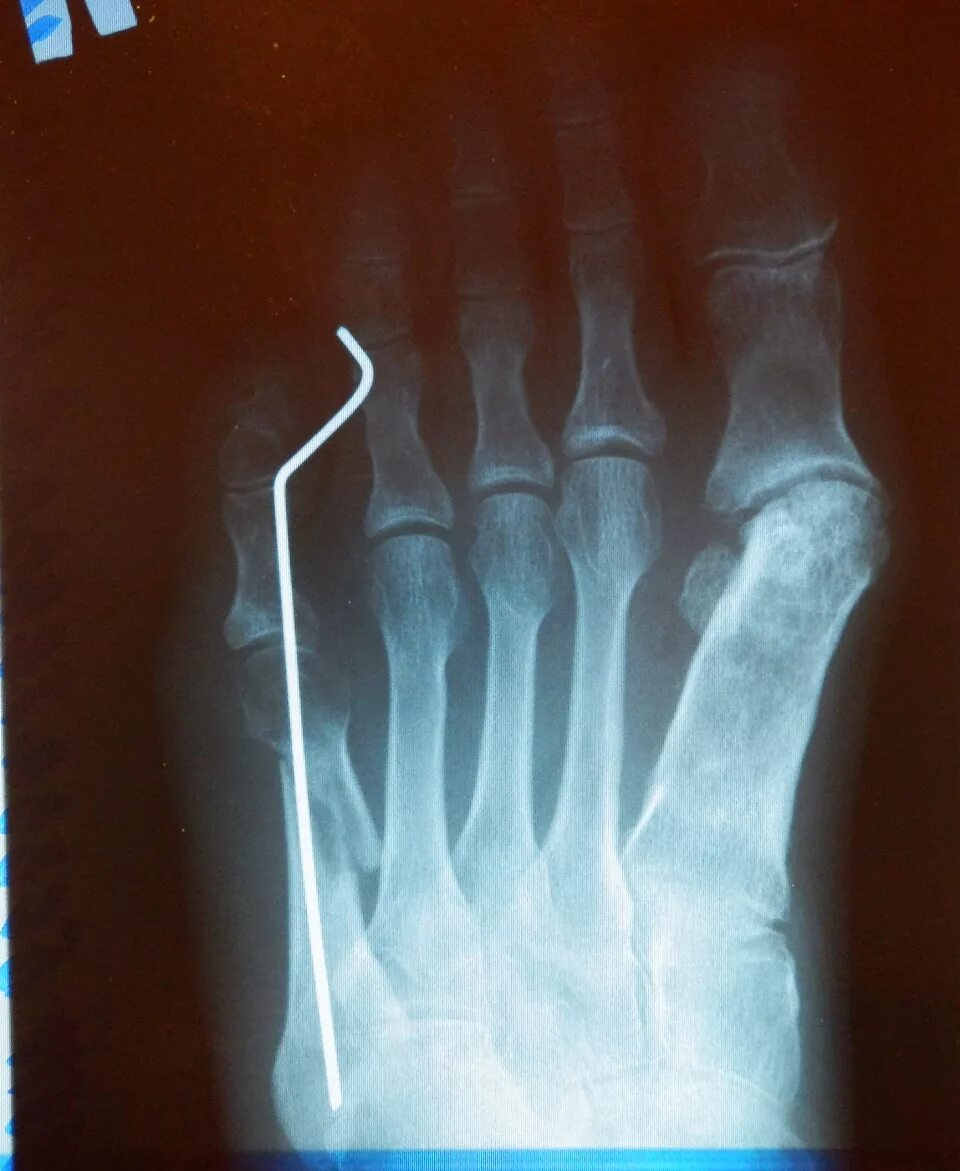

Остеосинтез 5 плюсневой кости. перелом пятой пястной кости спицы.

Перелом плюсневой кости кисти. субкапитальный перелом 4 плюсневой кости. остеосинтез 5 плюсневая кость. остеосинтез плюсневой кости спицами.